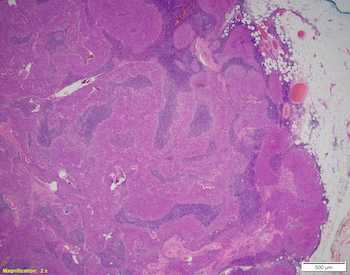

Thymomas are one of the most common tumors in the anterior mediastinum in adults. About 40% of cases are associated with paraneoplastic or autoimmune syndromes. Morphologically, these are epithelial tumors with bland spindle cells with a storiform pattern. Most cases lack necrosis and have a low Ki-67 index; however, these can be seen with atypical type A thymomas. They will stain strongly for epithelial markers (p40/p63) and will usually lack TdT-positive T-cells. Complete resection associated with overall survival even though about 20% of patients will have a Masaoka stage II or III tumors.